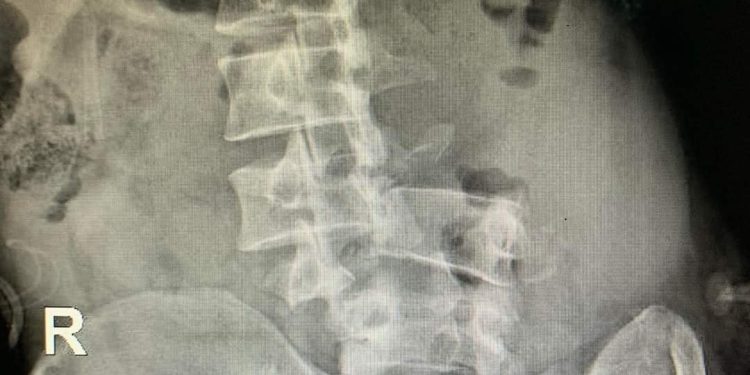

Hình ảnh X-quang gãy phức tạp cột sống thắt lưng

Kết quả CT – Scanner “Ít dịch ổ bụng, cơ thắt lưng chậu trái phù nề, tụ dịch chung quanh, tụ khí mô mềm hông lưng trái, dịch len lỏi giữa các cơ vùng lưng 2 bên. Gãy di lệch đốt sống L3 – 4 chèn ép tủy sống vùng này. Gãy mỏm ngang 2 bên L5; gãy mỏm ngang 2 bên, mỏm gai và thân đốt sống L4; mỏm ngang bên trái, mỏm gai và thân đốt sống L3. Gãy xương cánh chậu trái”.